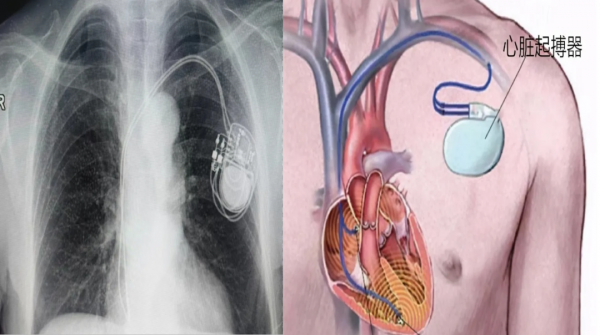

心臟起搏器植入

適用于嚴重心動過緩、竇房結功能不全、高度房室阻滯等。

案例:84歲女性,永久起搏器植入,總費用約5.9萬元。

手術微創(chuàng),局部麻醉,術后12小時可下床活動。